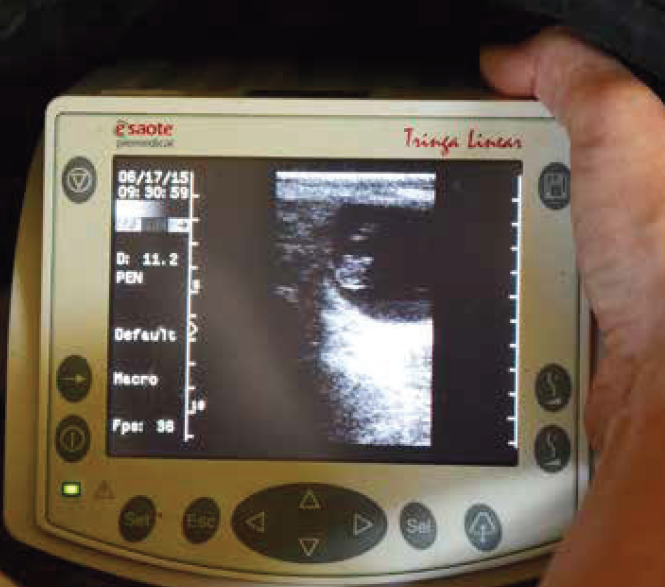

Tragend oder nicht tragend – das ist hier die Frage!